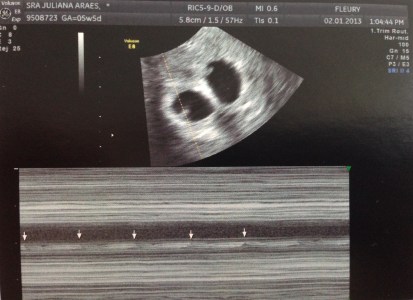

Foi então que, no dia da primeira ultrassonografia obstétrica, passei novamente por mais um dos momentos mais emocionantes da minha vida. Naquele dia, eu tive a resposta de Deus. Naquele dia, Deus me mostrou a vontade Dele, que era a de me tornar mãe de dois bebês. Naquele dia, eu agradeci a Ele infinitamente pela graça que nos foi concedida. Aliás, não só naquele dia, agradeço a Ele todos os dias.

Penso ser interessante mencionar que, no dia do meu primeiro ultrassom obstétrico, eu estava com 5 semanas e 6 dias. Lembrando que a data que marca o início da gravidez é a data da última menstruação (e não a data da transferência dos embriões).